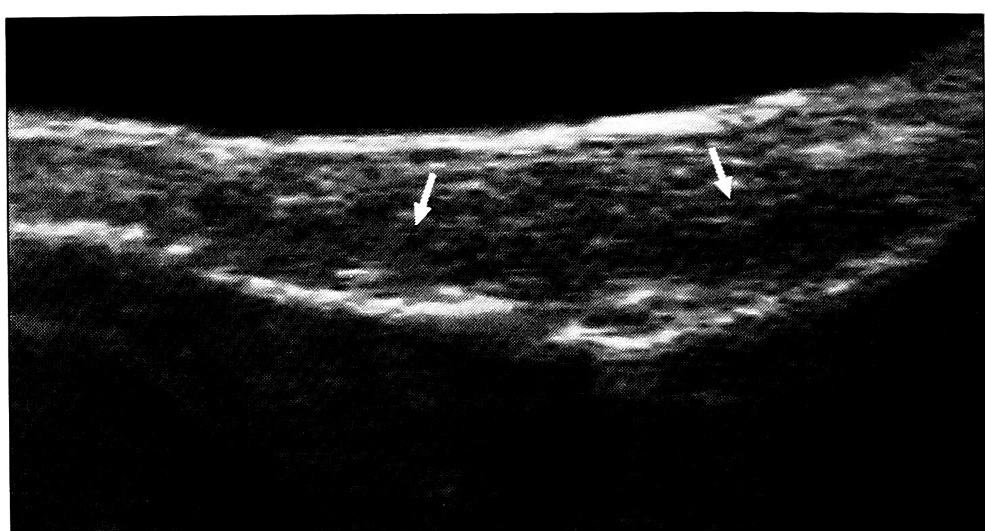

Свежие повреждения. Полные повреждения сухожилия на сонограмме характеризовались прерыванием его сплошного контура с появлением гипоэхогенной зоны дефекта (рис. 1).

Рис. 1. Продольная сонограмма поврежденного сухожилия разгибателя II пальца на уровне дистального межфалангового сустава (4-й день после травмы). Определяется дефект сухожилия (стрелка)